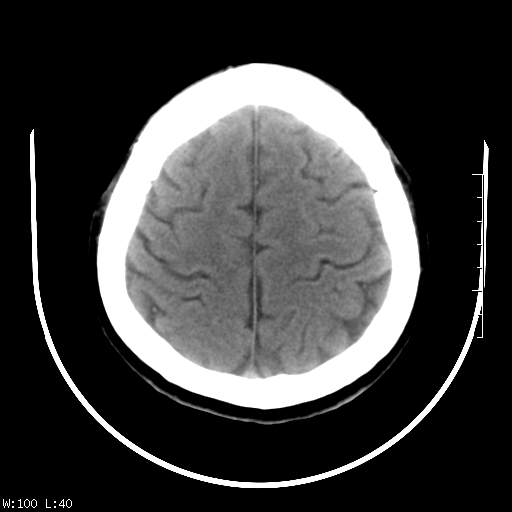

标题: CT22236:男,45,经常头痛。看看脑干正常吗? [打印本页]

标题: CT22236:男,45,经常头痛。看看脑干正常吗?

未见明显异常,建议ct增强或mri检查。

没见异常密度及形态改变啊,我认为是正常的。

颅脑ct轴位平扫颅内未见明确异常。

颅脑ct平扫未见明确异常,必要时mri检查。

颅脑ct平扫未见异常